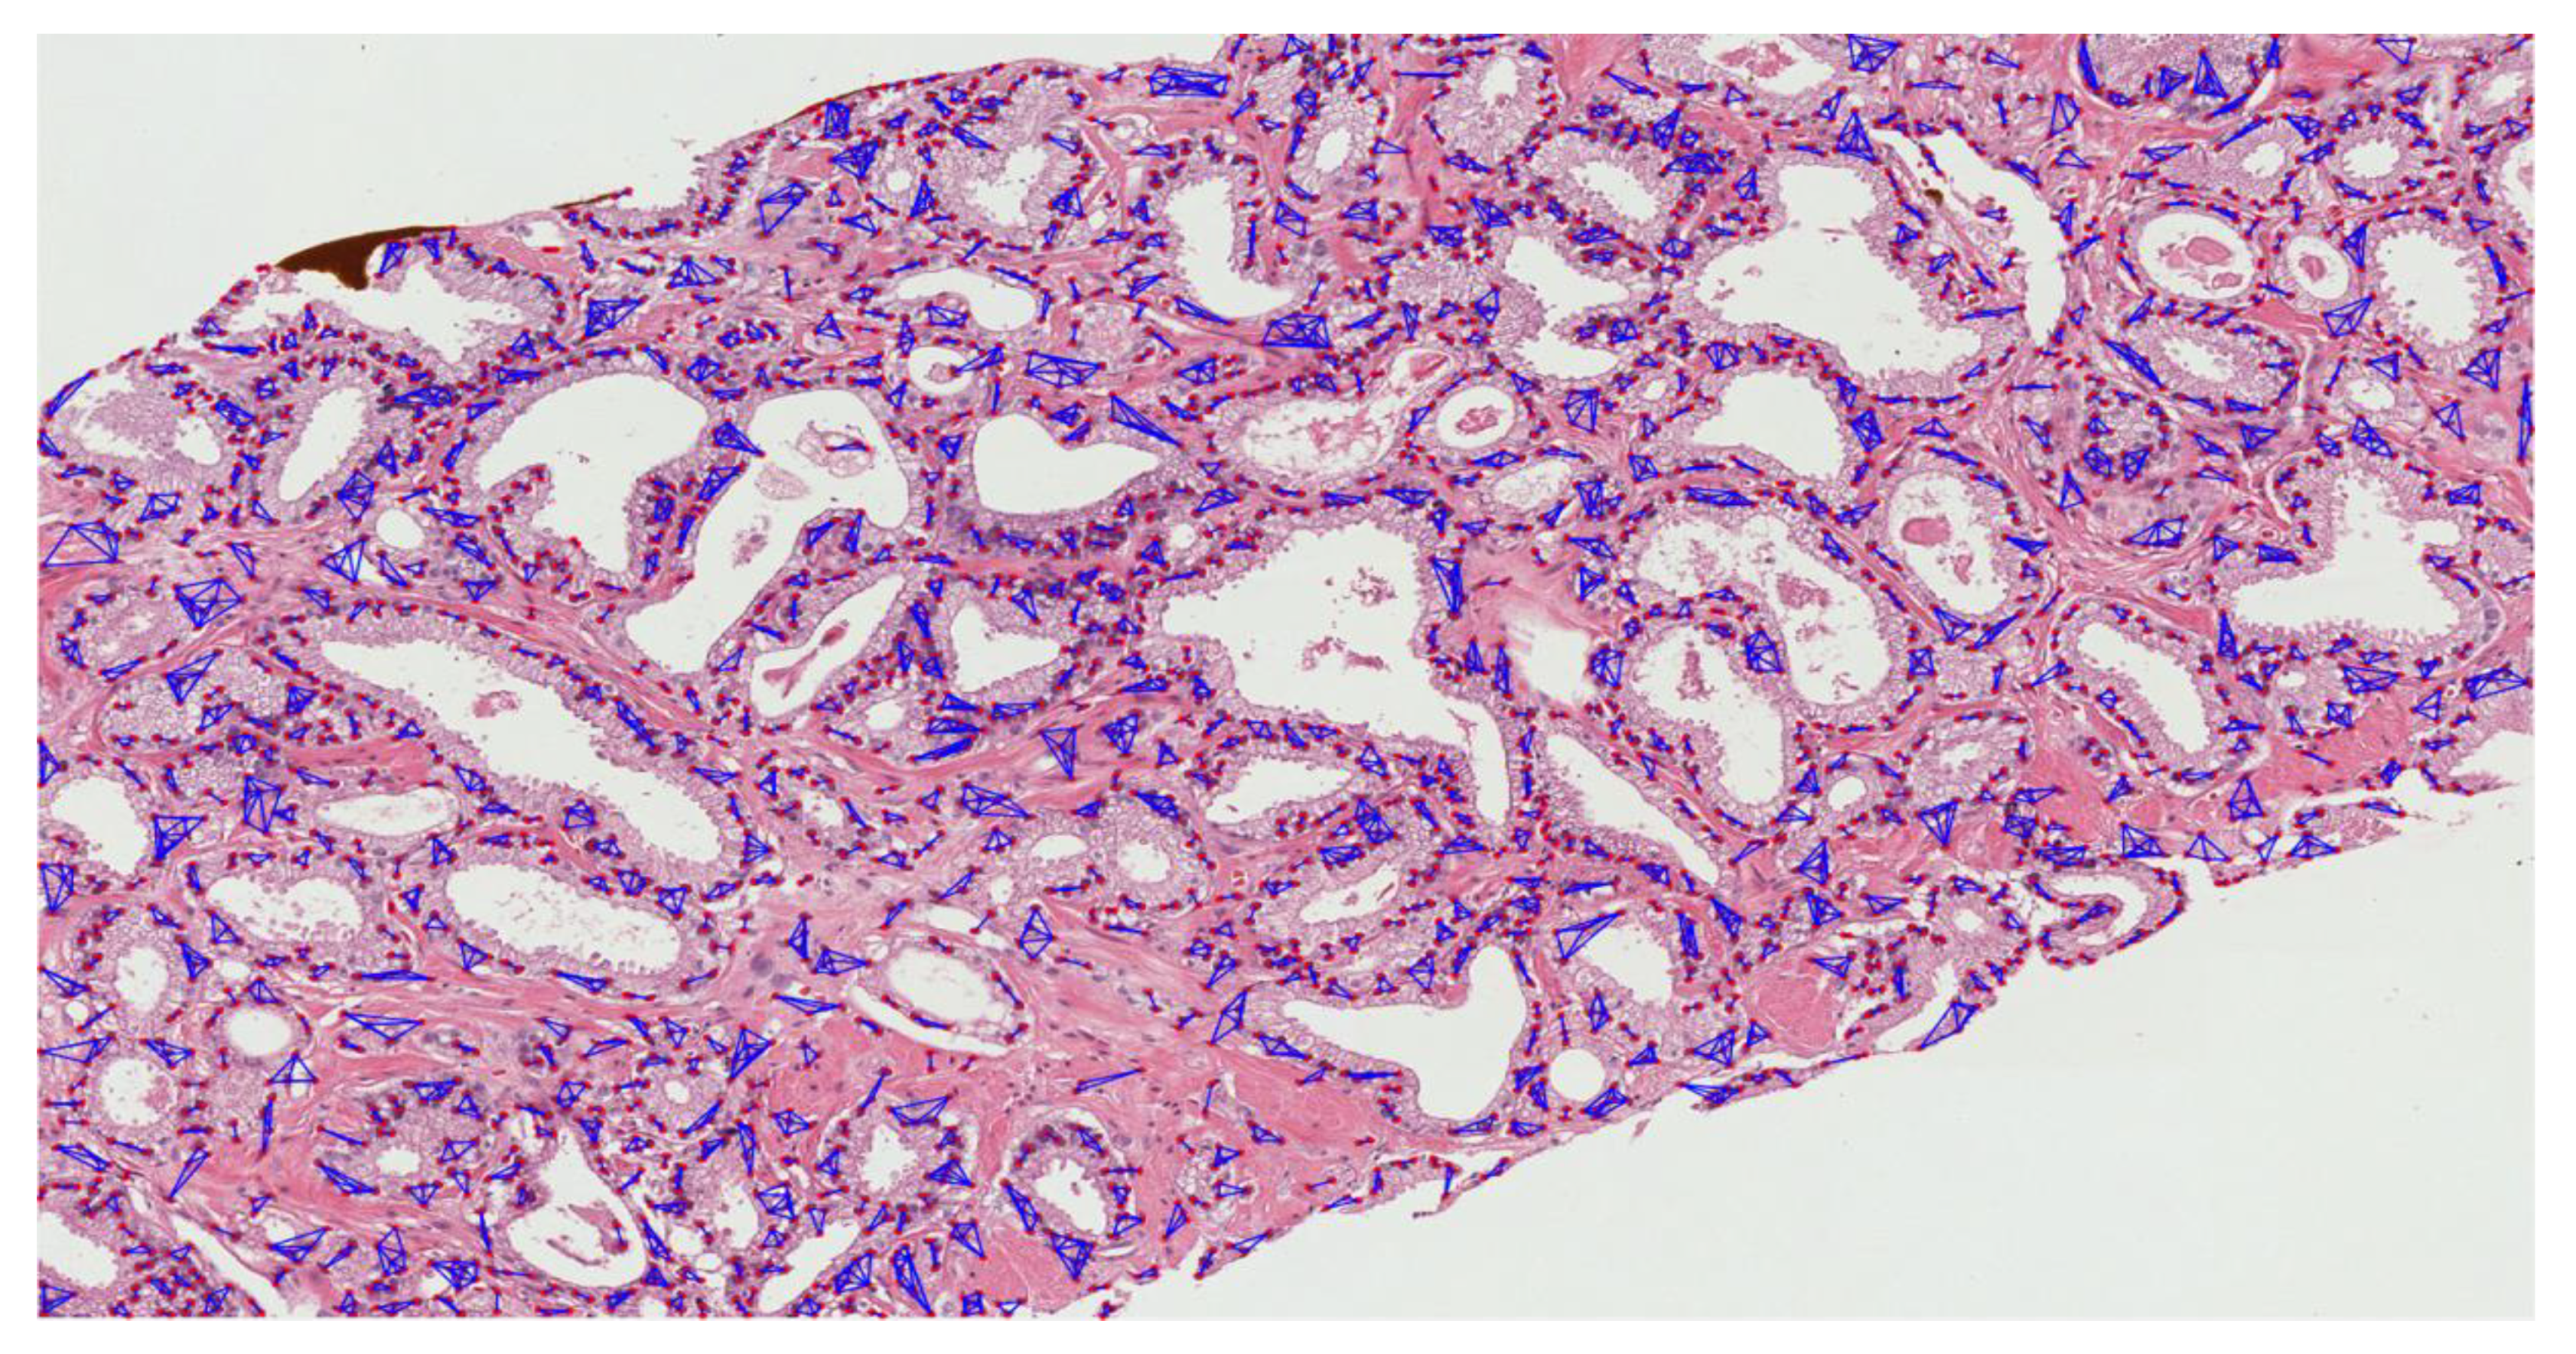

The MST cluster analysis method was applied on the PCa tissue samples of dataset 1 and dataset 2, and the visualization results of intra- and inter-cluster MST are shown in Figure 12. From the following figure, we can analyze that the structure and shape of the clusters in each grade are different from each other. It is quite challenging for researchers and doctors to analyze the microscopic biopsy images of PCa and identify suitable biomarkers compared to other common cancers.

Figure 12.

The visualization of intra- and inter-cluster MST graphs. (a–c) The intra-cluster MST of grade 3, grade 4, and grade 5, respectively. (d–f) The inter-cluster MST was generated from a, b, and c, respectively. The dotted red circle indicates the cluster of cell nuclei. Different color lines in a-c and d-f indicate intra- and inter-clusters, respectively.

The gold standard for the diagnosis of prostate cancer is a pathologist’s evaluation of prostate tissue. To potentially assist pathologists, DL-based cancer detection systems have been developed. Many of the state-of-the-art models are patch-based convolutional neural networks. Patch-based systems typically require detailed, pixel-level annotations for effective training. However, such annotations are seldom readily available in contrast to the clinical reports of pathologists, which contain slide-level labels. Our study sliced annotated and graded images from the pathologist, and we use an MST algorithm to perform cluster analysis and extract significant information for AI classification. The proliferation and cluster structure of cell nuclei, as shown in Appendix A, Figure A4 (Gleason pattern 3), Figure A5 (Gleason pattern 4), and Figure A6 (Gleason pattern 5), will help the pathologist to identify, classify, and grade more precisely the Gleason score assignment in the light of heterogeneity and variability.

The pathology annotated WSIs used in this research to analyze the pattern and community structure of cell nuclei in grades 3, 4, and 5, shown in Figure A1, Figure A2 and Figure A3, respectively. The cluster analysis was performed successfully on histological images of PCa. For visualization of the community structure of cell nuclei, we plot the clusters in the annotated regions of grade 3, grade 4, and grade 5 in WSIs, shown in Figure A4, Figure A5 and Figure A6, respectively.